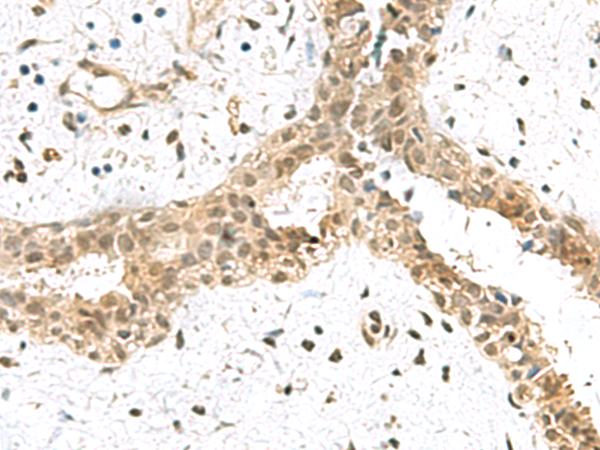

分类: 科研抗体货号: P10215别名: MAGED3; MAGE-d3应用: IHC反应种属: Human